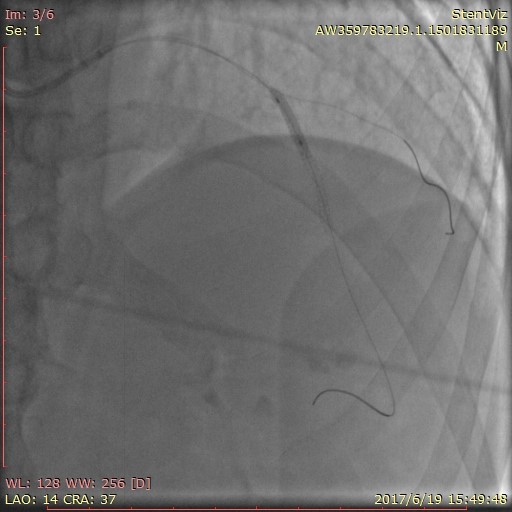

病例名称:支架精显功能在冠脉介入中的应用 病史: 男性,50岁 主因“间断胸痛半年,加重半天”入院。 曝光模式及参数: Dynamic,15f/s 造影表现: 经右桡动脉行CAG示:前降支中远段重度弥漫性狭窄。

治疗方案及结果: 前降支中远段重度弥漫性狭窄,行支架植入术治疗,术后罪犯血管开通,血流通畅,达TIMI3级。 病例点评及临床价值: 前降支近段支架释放后,发现支架球囊未完全扩张,后扩后情况未明显改善,应用StentViz示:前降支近段支架与远段支架重叠良好,近段支架近端未完全扩张,有“小腰”,呈“狗骨头效应”,同时血管局部钙化斑块明显。明确情况后,继续加压扩张后,支架完全扩张,血流通畅达TIMI3级。 在本病例中,术中StentViz即刻评价了支架释放效果,精准的显示了两支架扩张、重叠和贴壁的情况,把“几乎看不见的支架”精准的呈现了支架的每一个细节,同时也显示了透视和采集不易发现的钙化病变,提高了诊断的精准度,明确了进一步的治疗方案。